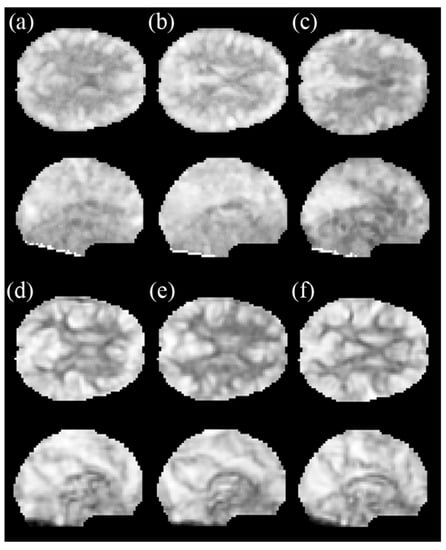

2.4. Amplitude of the Low-Frequency Fluctuations (ALFF)

2.5. Regional Homogeneity (ReHo)